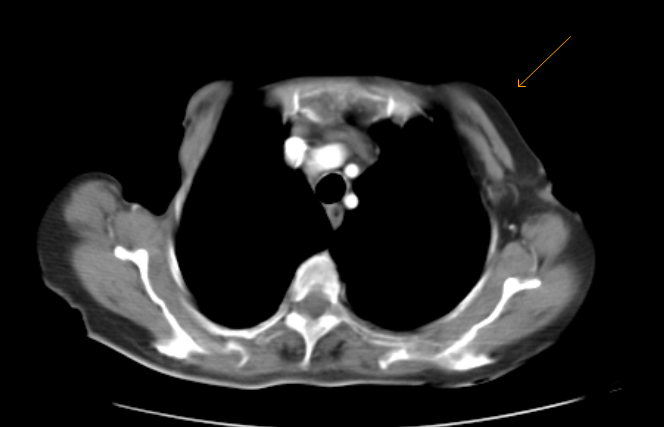

Poland’s Syndrome-CT - Sumer’s Radiology Blog

www.indianradiology.comsyndrome radiology

www.indianradiology.comsyndrome radiology

Poland Syndrome – Radiology Cases

radiologycases.myPoland Syndrome - Stock Image - C021/1675 - Science Photo Library

radiologycases.myPoland Syndrome - Stock Image - C021/1675 - Science Photo Library